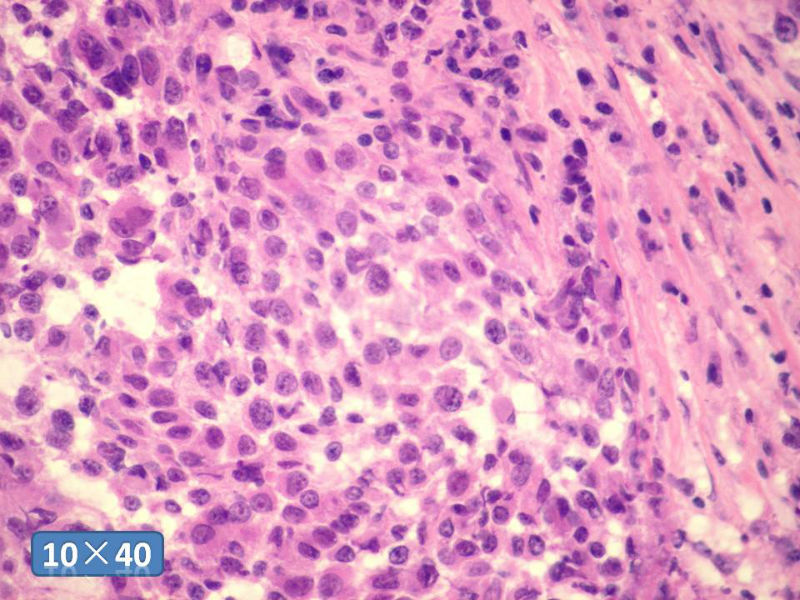

女性,50岁,乳腺肿物,冰冻切片(图1-25)

HE

IDC